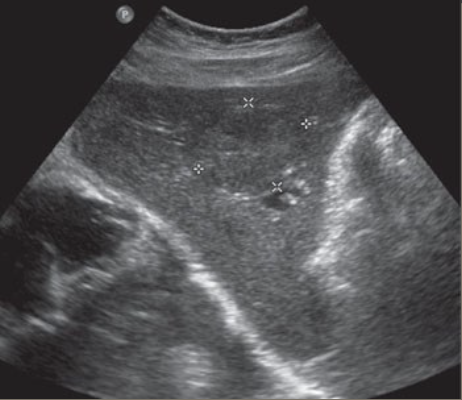

Cirrhosis → chronic liver disease causing fibrosis and scarring

clinical hx: EtoH abuse, older male, obesity, chronic hepatitis

s/sx: asymptomatic, can have abdominal discomfort/distention, anorexia/weight loss, jaundice, dark urine, abnormal AST & ALT, elevated bili

2D US: early stages → hepatomegaly, later/progressive → right ± left lobe atrophy, compensatory caudate lobe hypertrophy, fibrotic heterogenous liver changes, nodular contour, ± hepatic vein compression w/ flattened waveform, PHTN → ascites, splenomegaly, MPV dilation ± reversal of flow

DDX: chronic hepatitis (coarse, fibrotic liver, can turn into cirrhosis if prolonged)